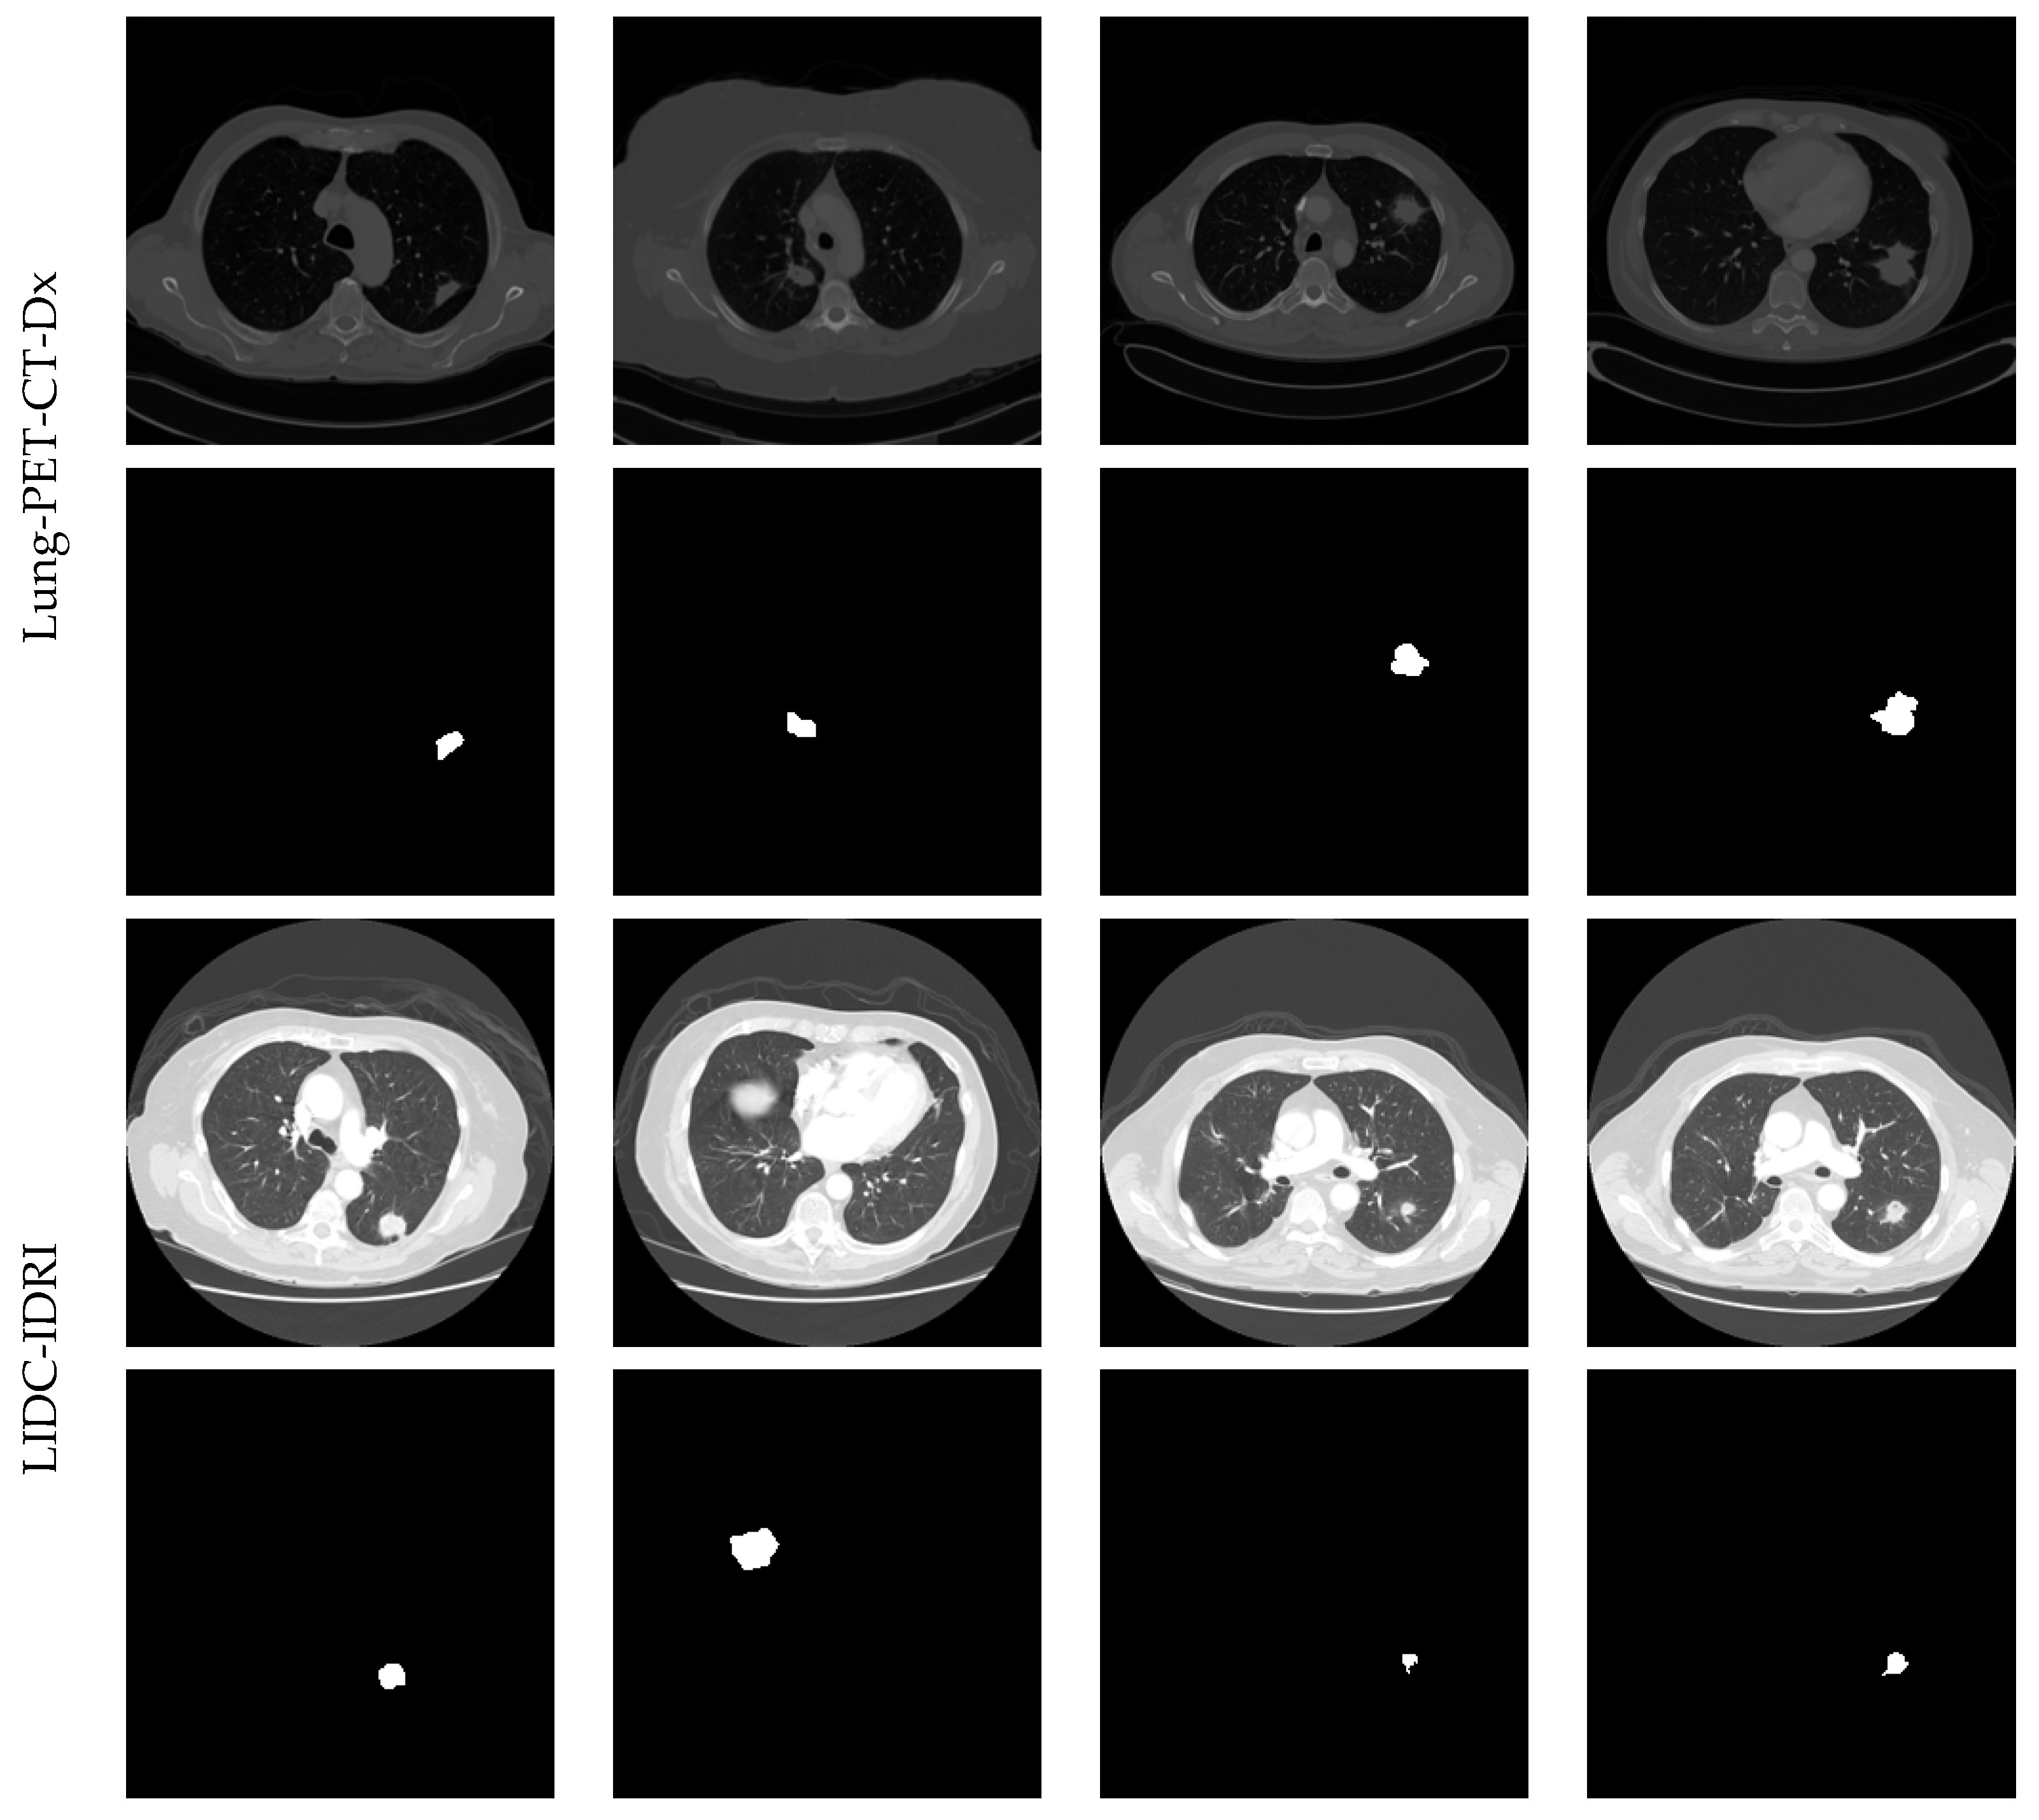

3.1. Image Database Preparation